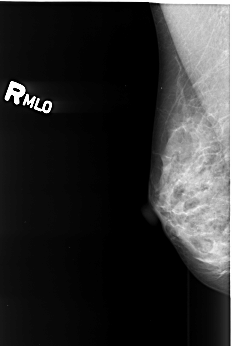

B_3418_1.RIGHT_MLO

RIGHT_CC LINES 3976 PIXELS_PER_LINE 2768 BITS_PER_PIXEL 12 RESOLUTION 50 NON_OVERLAY

RIGHT_MLO LINES 4144 PIXELS_PER_LINE 2784 BITS_PER_PIXEL 12 RESOLUTION 50 NON_OVERLAY